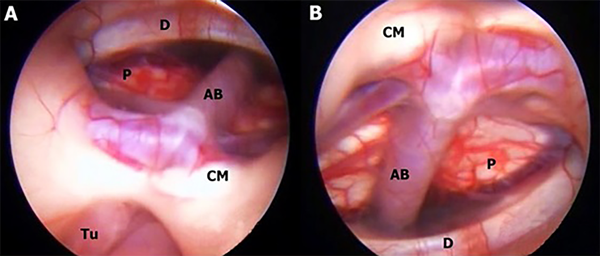

En este estudio fueron halladas 10 variedades anatómicas del piso anterior del tercer ventrículo, las cuales son en orden de frecuencia: piso opaco o grueso 54,90% (Figura 1), piso parcialmente borrado 29,41% (Figura 2), intervalo prepontino pequeño 23,53% (Figura 3), piso estrecho 17,65% (Figura 4 A-B), piso herniado 17,65% (Figura 5), piso delgado 11,76% (Figura 6), basilar elevando el piso 1,96% (Figura 4C-D), adherencias interhipotalámicas 3,92% (Figura 7), fenestración espontánea 1,96% (Figura 8), y piso sin reparos anatómicos 1,96% (Figura 9). Las primeras 7 según la descripción de Sughrue, a la cual se sustituye banda premamilar por adherencias interhipotalámicas, descriptas por Phillips4, fenestración espontánea al hallarse ausencia de PTV u ostomía espontánea como en la Fig. 8, reportada por Parmar5, y se introduce otra categoría no reportada, piso sin reparos anatómicos cuando no se pueden diferenciar los cuerpos mamilares ni el receso infundibular. En la mayoría de los casos se detectaron 2 o más variedades.

Figura 8: A-B: Mujer de 34 años con tumor a nivel de región pineal, hidrocefálica, presentándose con síndrome de Parinaud, por lo que se decide realizar TVE más biopsia, observándose en el intraoperatorio fenestración espontánea del PTV con ausencia total de Membrana de Liliequiest. AB arteria basilar; CM cuerpo mamilar; D dorso selar; P puente; Tu tumor.